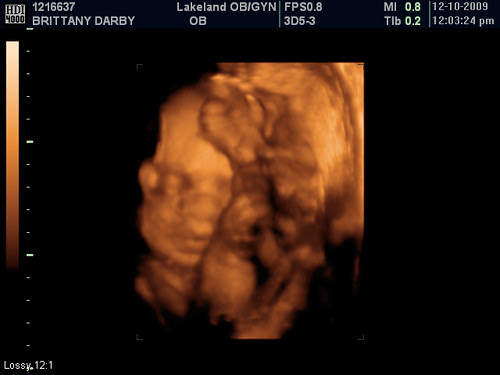

Photo of the Day - That's My Boy:

Today was the big day! After our first Dr. appointment which was just a routine check up we had our 4D sonogram. I have been pumped up about it all week! I guess baby Darby didn't really get the memo to be awake and ready to go so he turned out to be a pretty difficult one. He was definitely not very active and actually had his hands (and feet) up over and in front of his face. He was definitely comfortable but not the easiest to photograph. Brittany and I joked that we should schedule this for around midnight since he is definitely WAY more active right before we head to bed. The sonogram technician did an amazing job and was so patient and actually took a little extra time to make sure we got some pics of him. That really meant a lot to both of us and made the experience special. Here are a few others from the sonogram:

Thanks so much for stopping by and hopefully you can see what is going on in some of those shots and you can actually decipher what is going on in there. Seeing him was great but it only makes me even more impatient to be able to finally meet him in person! Be sure to stop by tomorrow for a 2D Friday photo of the day. :-)